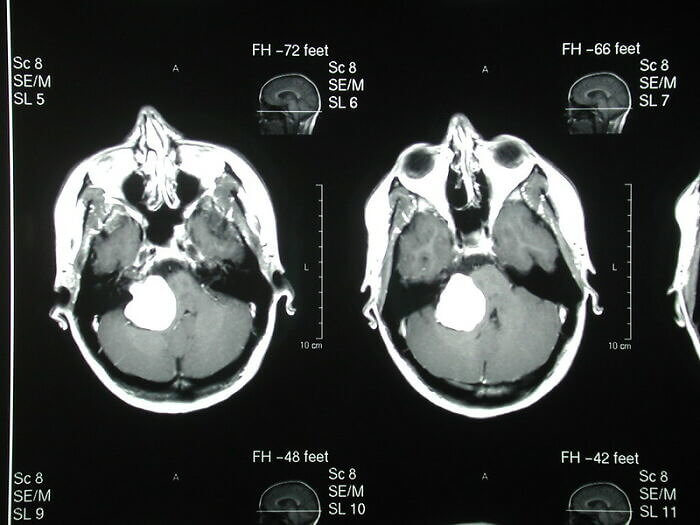

Locked In Syndrome Is Real

Can you imagine being in your body but unable to move or speak to let anyone know that you are conscious? It sounds like the makings of a medical horror movie because this does happen in real life. About 1 percent of people who have strokes and end up in a coma are actually conscious but unable to open their eyes and communicate easily. This is called Locked-In syndrome, and one notable case involved a man named Richard Marsh who appeared to not have any brain function after a stroke.

His doctor had been watching him when he decided to lift up his eyelids to see if there was movement. He could move his eyes enough for 'Yes' and 'No' answers, and his doctor was able to help him recover.